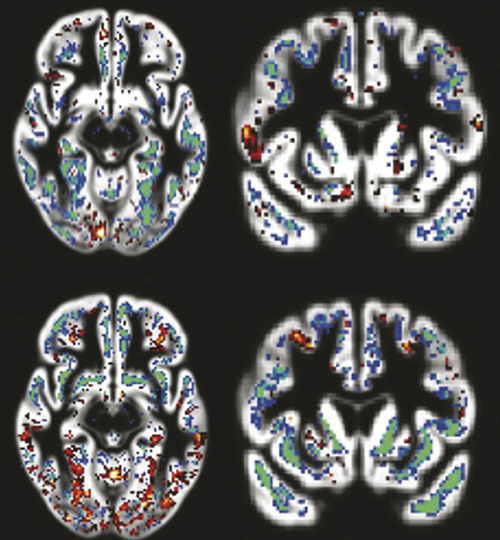

Ces anomalies biologiques cérébrales sont maintenant explorées in vivo par des bio­marqueurs du liquide cérébrospinal et peut-être bientôt du sang, ou par imagerie par émission de positons grâce à de nouveaux traceurs. La physiopathologie pourrait commencer par une accumulation anormale de peptide amyloïde suivie d’une agrégation anormale de protéine tau, ou de tau anormalement phosphorylée, mais d’autres facteurs pourraient intervenir comme facteurs d’aggravation ou de protection, tels que la neuro-­inflammation et l’activation des cellules microgliales, les facteurs vasculaires que sont les micro-lacunes, les micro-saignements et les anomalies de la barrière hémato- encéphalique ou enfin la réserve cognitive.